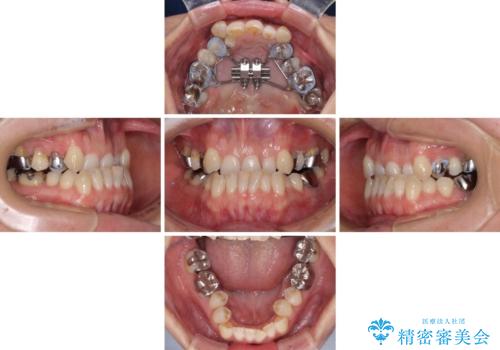

上顎骨の幅が下顎骨よりも小さいので、拡大装置により骨幅を広げて上下関係を改善すると同時にワイヤー矯正で反対咬合の改善を図り、その後インビザラインにて歯並びを整えることとしました。

急速拡大装置の使用により奥歯の咬み合わせが劇的に変わり、その変化を利用して反対咬合を改善することができました。

治療期間中は奥歯が咬み合わず、食事が取りにくいなどの不都合がありましたが、最終的にはきれいに整えることができました。